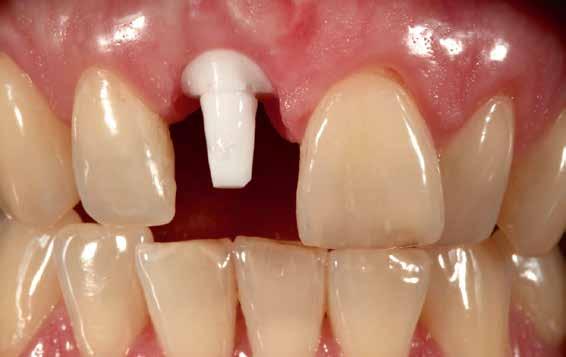

A felső frontfogak állapota elhanyagolt, a parodontális struktúrák részben erősen károsodottak, VMK korona az 12 zónában, az ínyszél szürke, fekete approximális háromszögek… vörös-fehér esztétikáról nem is beszélhetünk (1. kép). Így jelentkezett a hölgypáciens a Weston Dental Specialists Group rendelőben. Elvárásai magasak voltak. A defektusok kezelését, a gingiva lefutásának korrigálását kívánta. Gyorsan világossá vált, hogy a megoldást csak a négy frontfog teljes kerámiakoronával való ellátása jelentheti. A jelen eset bemutatja, hogy az IPS e.max ZirCAD Prime segítségével hogyan lehet tiszta, tetszetős és esztétikus mosolyt létrehozni.

1. kép: Kiindulási helyzet.